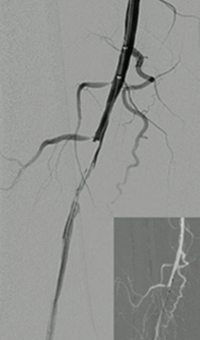

Pharmacomechanical revascularization of extensive iliofemoral thrombus

60 year old female presented with 4 weeks calf pain 1 week swelling.

Procedural steps

• Power Pulse delivery 10mg tPA

• 20 minute dwell time

• ZelanteDVT runtime 415 seconds

• Total case time 90 minutes

Xray of Iliofemoral thrombus pre-treatment and Power Pulse™ delivery

Iliofemoral thrombus pre-treatment (left) and Power Pulse delivery (right)

Xray of veins post-ZelanteDVT mechanical thrombectomy.

Post-ZelanteDVT  Mechanical Thrombectomy

Xray of veins post-ZelanteDVT runtime 415 seconds.

Post-ZelanteDVT runtime 415 seconds

Images Courtesy of Charles Wyble M.D. – Vascular Surgical Associates, Marietta, Georgia – January 5, 2016